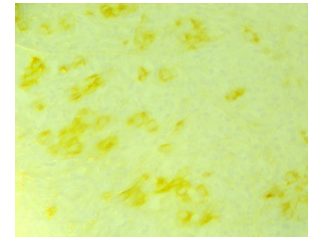

On anatomopathological examination, the duodenal mucosa was largely dissociated by a polymorphous, lymphoplasmacytic inflammatory granulation tissue with numerous neutrophils comprising large cells with fine chromatin and a visible nucleolus with individualization of a few figures of mitosis (Figure 1). The immunohistochemical study confirmed that the large cells expressed intense and diffuse cytokeratin and MUC1 and focal cytokeratin 7. In addition, CDX2 was negative on tumor cells (Figure 2).

Figure 1: Histological study: the duodenal mucosa was largely dissociated by a polymorphous, lymphoplasmacytic inflammatory granulation tissue with numerous neutrophils comprising large cells with fine chromatin and a visible nucleolus with individualization of a few figures of mitosis.